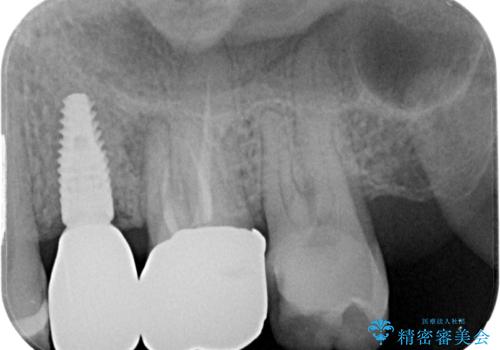

- 銀歯がとれたのでやり替えたいとのことで来院された患者様です。何度も同じ部位の銀歯の脱離を繰り返しており、メタルインレーの不適合も認めていたためオールセラミッククラウンにて補綴治療を行っていくことにしました。

拡大鏡視野下で、セラミックの被せもの、虫歯の除去を行い、オールセラミッククラウンに適した形に整えました。

歯と歯茎の間に圧排糸と言われる糸を入れてシリコーン印象材にて型どりをしました。